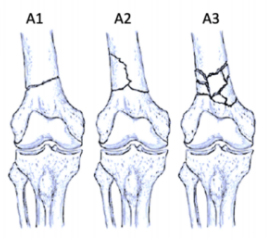

股骨远端骨折可根据骨折模式、部位和膝关节受累情况进行分型 ,AO/OTA分型常用于对这些骨折进行分类。在每个类别中,骨折可根据复杂性和移位程度进一步分类,对于与全膝关节置换术(TKA)相关的假体周围股骨远端骨折,基于骨折移位和TKA股骨假体完整性的Lewis和Rorabeck分型(1997年)是最常用的分型:

A型:关节外骨折

不累及关节面

B型:部分关节内骨折

累及部分关节面但保持一定的关节匹配性

C型:完全关节内骨折

关节面完全破坏